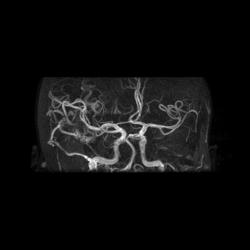

Артерио-венозная мальформация сосудов головного мозга.

Аксиальный срез на уровне мальформации

Корональный срез на уровне мальформации

Сагиттальный срез на уровне мальформации

При МР-ангиографии в режиме 3D TOF и 2D-TOF SPGR без применения контрастирующих веществ:

- определяется клубок расширенных и извитых патологических сосудов, получающих артериальную кровь из средней оболочечной артерии (ветвь наружной сонной артерии),  последняя расширена, из средней мозговой артерии и из задней мозговой артерии, эти артерии также шире, чем артерии контрлатеральной стороны. Дренирующие вены впадают в область стока синусов, а также в задний отдел верхнего сагиттального синуса

- внутренняя сонная, передняя мозговая, задняя соединительная  артерии симметричны, сигнал от них не изменен

- дополнительно отмечены расширенные и извитые экстракраниальные сосуды, преимущественно под правой половиной задней черепной ямки.